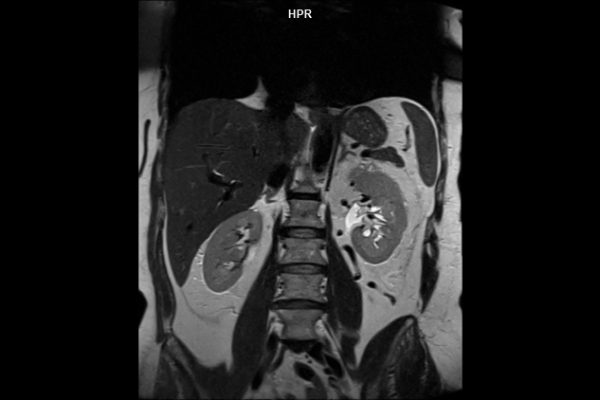

Detailbild MRT